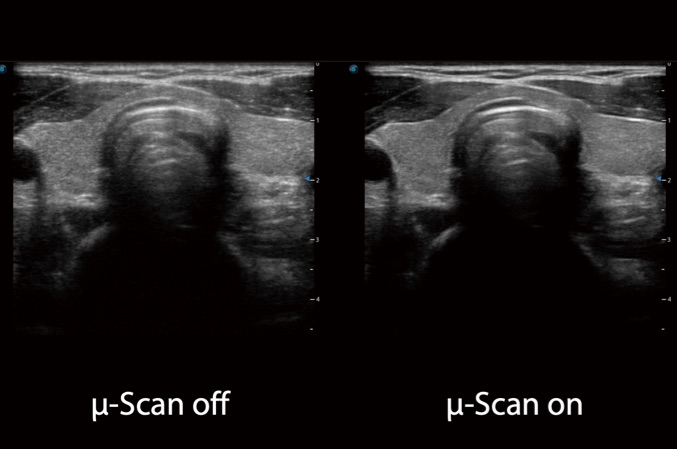

• μ-Scan+

La tecnología de imagen μ-Scan de nueva generación le ofrece una mejor calidad de imagen reduciendo el ruido, realzando la uniformidad de la imagen y mejorando la continuidad de los límites para obtener detalles reales y una visualización mejorada.